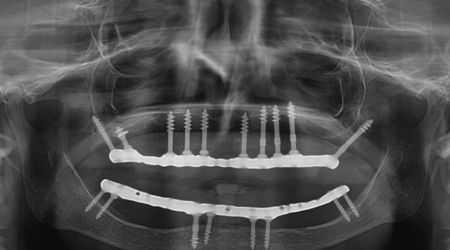

Dental Implant Packages (Lower Jaw)

Technique INR US

8 implants + 14 units Metal-free bridge (Zirconia) 350000 5400

8 implants + 14 units Ceramic bridge (Porcelain fused to metal) 300,000 4500

Dental Implant Packages (Upper Jaw)

10-12 implants including 2 Pterygoid implants + 14 units Metal-free bridge (ZIRCONIA) 400,000 6200

10 implants including 2 Pterygoid implants + 14 units Ceramic bridge (Porcelain fused to metal) 350,000 5500

Full Mouth Rehabilitation with 6-8 Implants Protocol for good bone

Upper Jaw/Lower Jaw (Per Jaw)- NOBEL BIOCARE

6-8 NOBLE BIOCARE Implants + 12 to 14 Units Metal Ceramic Bridge (Porcelain Fused to Metal 350000 5400

6-8 NOBLE BIOCARE Implants + 12 to 14 Units ZIRCONIUM (Metal Free) CERAMIC BRIDGE 500000 7600

Upper Jaw/Lower Jaw (Per Jaw)- ADIN

6-8 ADIN Implants + 12 to 14 Units Metal Ceramic Bridge (Porcelain Fused to Metal) 250000 3800

ALL- ON -4 FOR LESS BONE

Upper Jaw/Lower Jaw (Per Jaw)

4 NOBEL BIOCARE Implants including 2 ANGULATED Implants + IMMEDIATE Provisional Denture + Final Fixed Titanium Hybrid Denture of 12-14 Teeth 350000 5400

4 NOBEL BIOCARE Implants including 2 ANGULATED Implants + IMMEDIATE Provisional Denture + Final Fixed PROCERA Implant Bridge Denture of 12-14 ZIRCONIA Ceramic Crown 500000 7600

ALL- ON -4 WITH ZYGOMA IMPLANTS (FOR MINIMAL BONE)

Upper Jaw

4 NOBEL BIOCARE Implants including 2 ZYGOMA Implants + IMMEDIATE Provisional Denture + Final Fixed TITANIUM HYBRID Denture of 12-14 Teeth 650000 10000

4 NOBEL BIOCARE Implants (QUAD ZYGOMA)+ IMMEDIATE Provisional Denture + Final Fixed TITANIUM HYBRID Denture of 12-14 Teeth 800000 12300